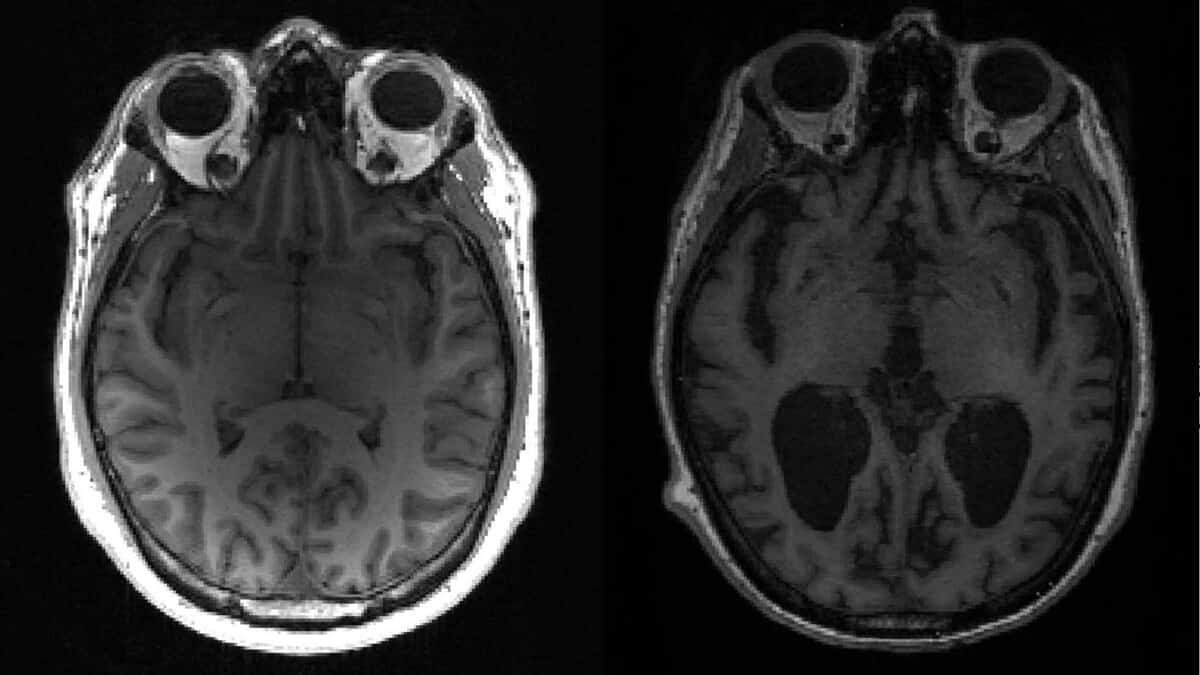

Plusieurs traitements antipsychotiques sont associés à de graves effets secondaires quand ils sont utilisés pour calmer des symptômes de démence comme la maladie d’Alzheimer, pointe une étude publiée jeudi, alimentant les controverses déjà nombreuses autour de ces médicaments.

«L’emploi d’antipsychotiques (...) chez les adultes atteints de démence est associé à des risques accrus d’accident vasculaire cérébral, de maladie thromboembolique veineuse, d’infarctus du myocarde, d’insuffisance cardiaque, de fracture, de pneumonie et d’insuffisance rénale aigüe», énumère cette étude parue dans le British Medical Journal (BMJ).

Mais il arrive aussi qu’ils soient prescrits à des patients atteints de démences, comme Alzheimer. Il ne s’agit pas de guérir ces maladies, la plupart du temps incurables, mais de calmer certains symptômes comme un comportement agressif.